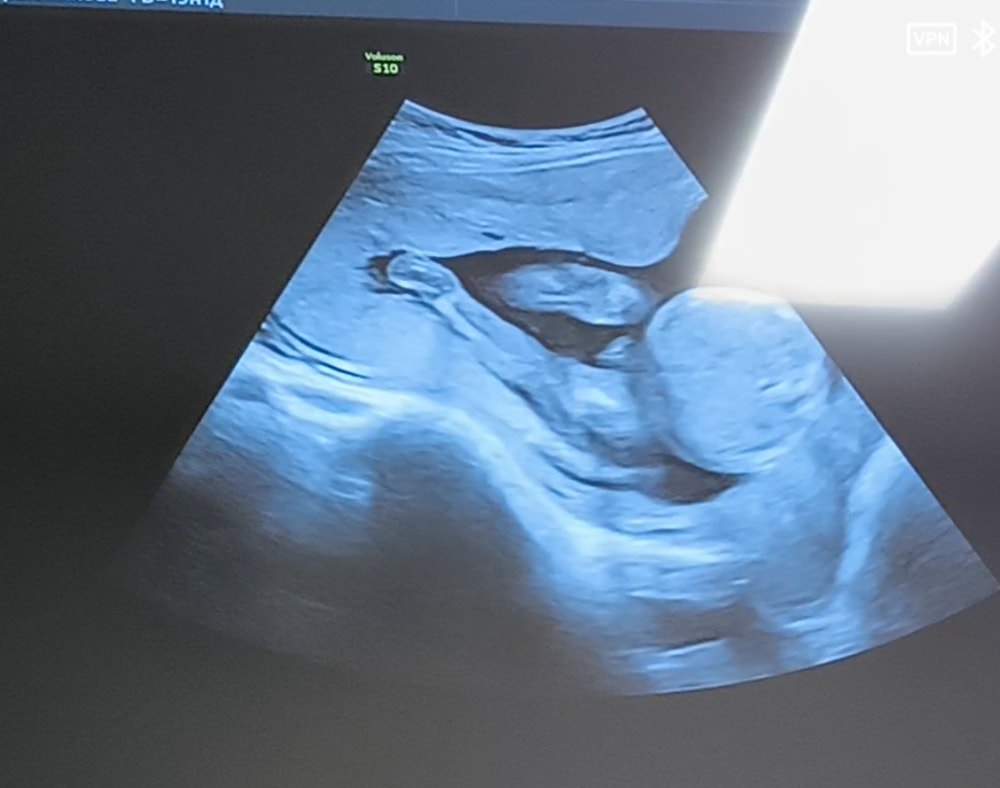

Анализы, скринингиНу что же , 25.11 на сроке 19.3 прошла второй скрининг) Врач сказала что все у нас хорошо, все соответствует норме, слава богу🙏 29 ноября устроим семейный гендер пати, в коробочке будут пинеточки с бантиком нужного цвета, и карточка у вас будет мальчик или девочка 🩷 открывать коробочку будет моя доченька, ей почти 1 годик и 5 месяцев) ещё когда в первом триместре у меня был жуткий токсикоз, я думала что будет девочка, после токсикоза хз, но смотря на видео с УЗИ думаю все таки вторая доченька у нас)

Я так и не стала разбираться в видео на УЗИ 😁только понимаю крупные четкие моменты, типо рука, нога, голова, сердечко бьётся косточки) а вот пол увидеть даже в постах у других девочек ничего не понимаю)